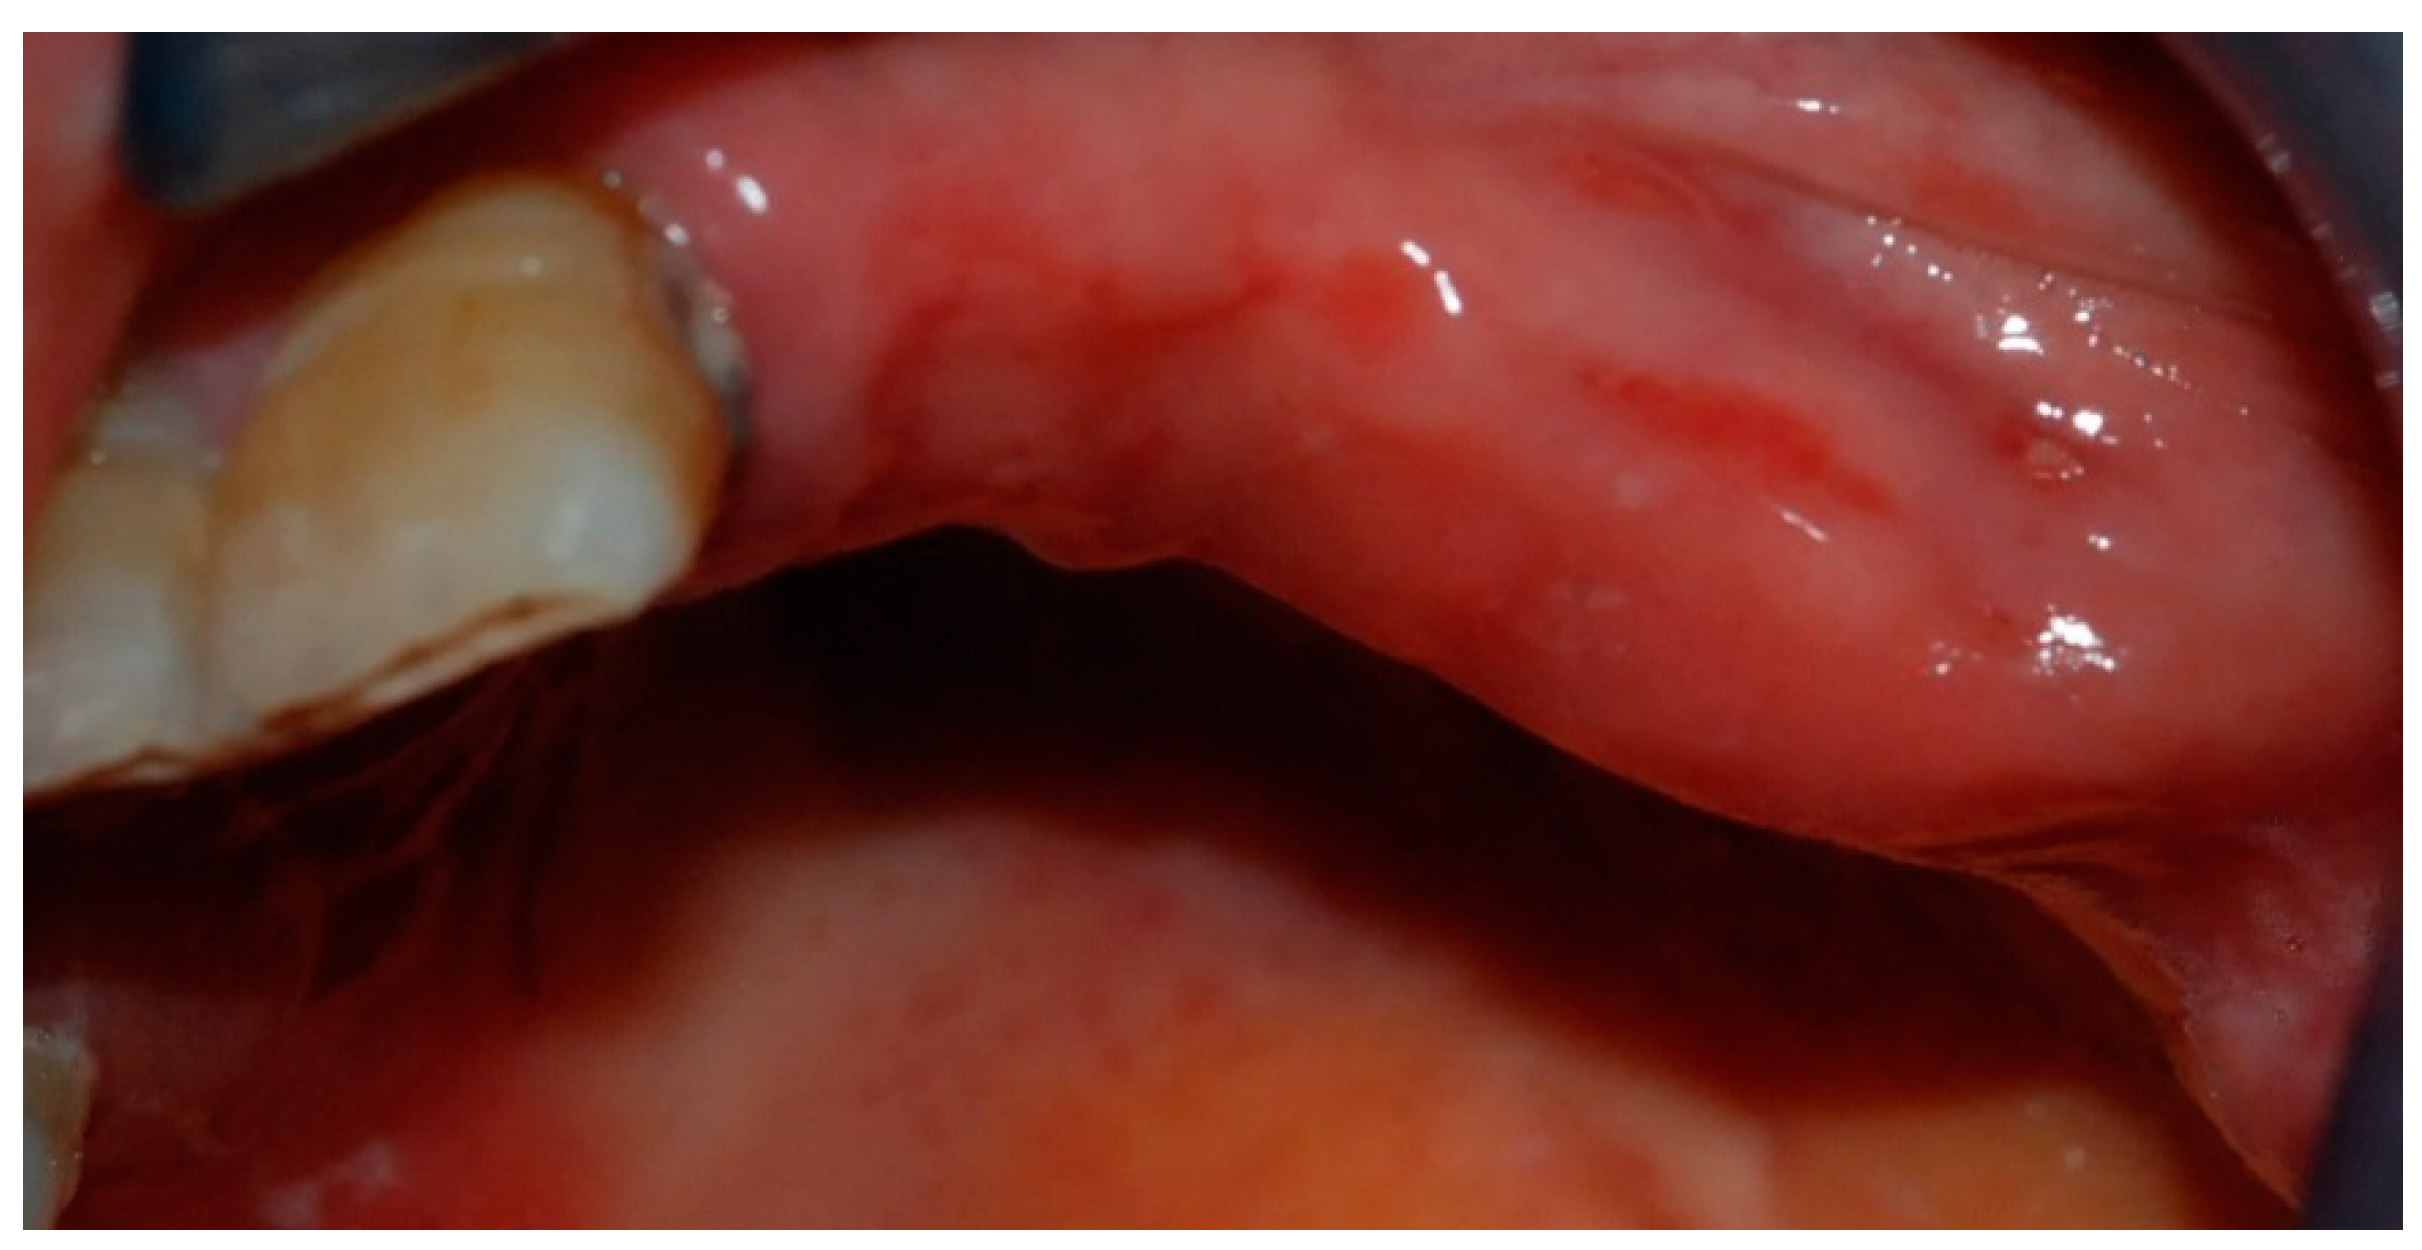

2. Case Report